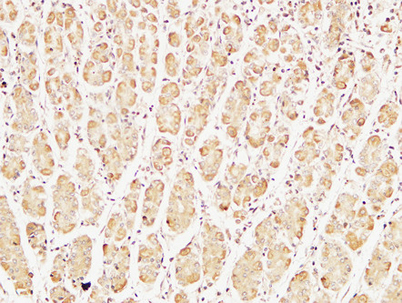

Caspase-7 rabbit pAb

Product name: Caspase-7 rabbit pAb

Reactivity: Human;Rat;Mouse;

Alternative Names: CASP7; MCH3; Caspase-7; CASP-7; Apoptotic protease Mch-3; CMH-1; ICE-like apoptotic protease 3; ICE-LAP3

Dilutions: Western Blot: 1/500 - 1/2000.IHC-p:1:50-300 ELISA: 1/20000. Not yet tested in other applications.

Immunogen: The antiserum was produced against synthesized peptide derived from human Caspase-7. AA range:45-94

Cellular localization: Cytoplasm.

Background: This gene encodes a member of the cysteine-aspartic acid protease (caspase) family. Sequential activation of caspases plays a central role in the execution-phase of cell apoptosis. Caspases exist as inactive proenzymes which undergo proteolytic processing at conserved aspartic residues to produce two subunits, large and small, that dimerize to form the active enzyme. The precursor of the encoded protein is cleaved by caspase 3 and 10, is activated upon cell death stimuli and induces apoptosis. Alternatively spliced transcript variants encoding multiple isoforms have been observed for this gene. [provided by RefSeq, May 2012],